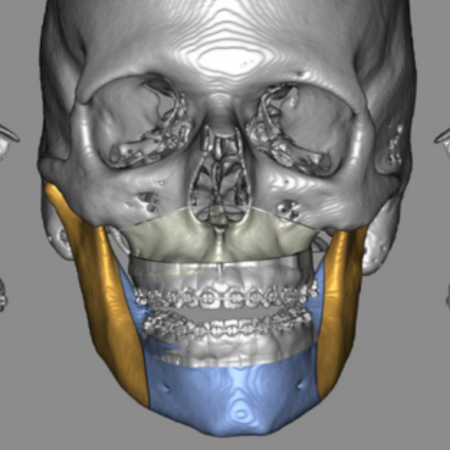

Objetivo: Este trabalho teve como objetivo comparar um novo método de oclusão digital automática, para planejamento cirúrgico virtual em cirurgia ortognática, com um método de oclusão digital e outro método manual convencional. Metodologia: Foi realizado um estudo de validação, com uma amostra de conveniência composta por 20 pacientes, sendo 7 do sexo masculino (35%) e 13 do sexo feminino (65%). Dois avaliadores, de forma independente, determinaram a oclusão final de cada...

Objective: This study aims to compare a new automatic digital occlusion method, for virtual surgical planning in orthognathic surgery, with a conventional digital method and a manual occlusion method. Methodology: A validation study was carried out, with a convenience sample consisting of 20 patients, 7 males (35%) and 13 females (65%). Two evaluators independently determined the final occlusion of each patient, using a conventional manual method, a digital method and an automatic digital...